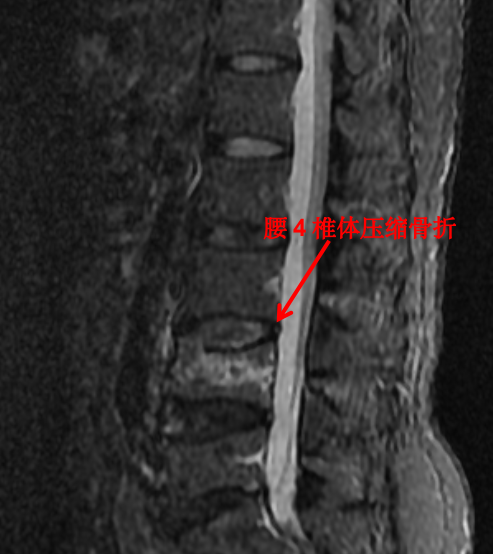

MRI 檢查

隨著科技進(jìn)步及醫(yī)學(xué)的發(fā)展,核磁已經(jīng)是脊柱外科不可或缺的檢查手段。對(duì)脊柱、韌帶、椎間盤(pán)、椎管內(nèi)神經(jīng)及椎旁組織顯影都優(yōu)于 CT,通過(guò)腰椎核磁我們可以直觀地看到椎間盤(pán)突出的程度、神經(jīng)受壓的程度,以及壓縮骨折的新鮮程度。

這對(duì)于脊柱疾病的治療有著很重要的指導(dǎo)作用。優(yōu)點(diǎn)是對(duì)脊柱及周圍組織顯影更清楚,無(wú)輻射。其缺點(diǎn)是價(jià)格昂貴,檢查時(shí)間長(zhǎng),有幽閉恐懼癥的患者難以接受。

前面提到的腰椎壓縮骨折,X 光片可以看出楔形變,但無(wú)法判斷新鮮骨折還是陳舊骨折,進(jìn)一步完善腰椎 MRI 才能明確診斷,做出下一步治療計(jì)劃。